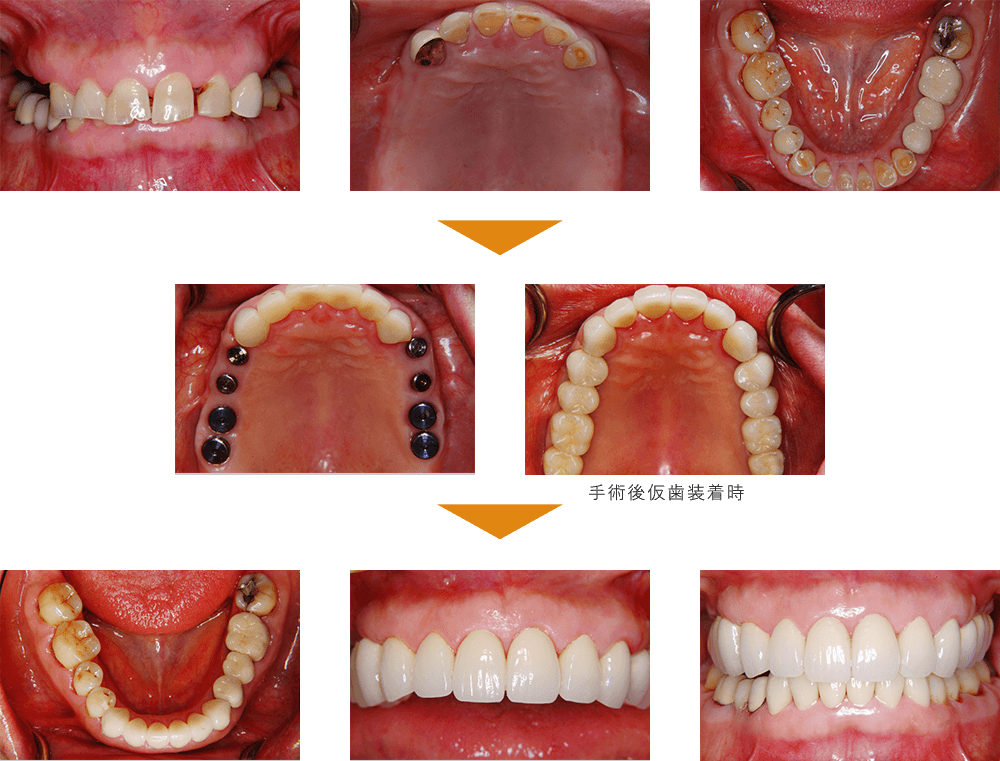

症例3

奥歯(臼歯) インプラント埋入

| 治療期間 | 約4カ月 |

| 費用 | 6,545,000円(税込) |

※状態により、骨補填等別途で費用が発生する場合もございます。

症例4

その他の即日荷重インプラント

| 治療期間 | 約4カ月 |

| 費用 | 下顎 5,170,000円(税込) |

※状態により、骨補填等別途で費用が発生する場合もございます。